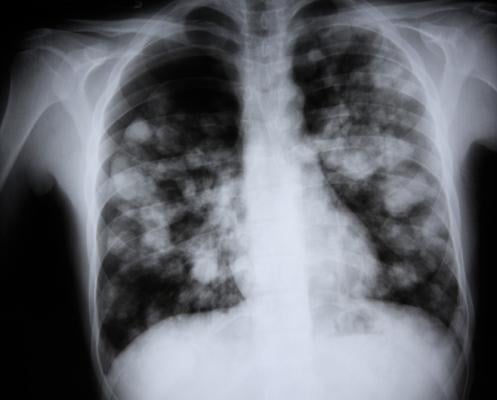

December 15, 2021 — Diagnosis of community acquired pneumonia in children usually involves X-rays, despite recommendations to limit their use by professional societies. In efforts to reduce radiation exposure from x-rays in children and reinforce guideline compliance, researchers from Ann & Robert H. Lurie Children’s Hospital of Chicago and colleagues developed a simple diagnostic model that accurately predicts whether patients are at high risk or low risk for community acquired pneumonia, eliminating the need for X-ray confirmation. Their findings were published in the journal Pediatrics.

Ramgopal and colleagues statistically derived their model based on the clinical history, symptoms and X-ray results of 1,142 patients, aged 3 months to 18 years who were evaluated for suspicion of community acquired pneumonia. They found three key variables with the strongest predictive value for either high risk or low risk of pneumonia – increasing age, fever duration and decreased breath sounds upon exam with a stethoscope.